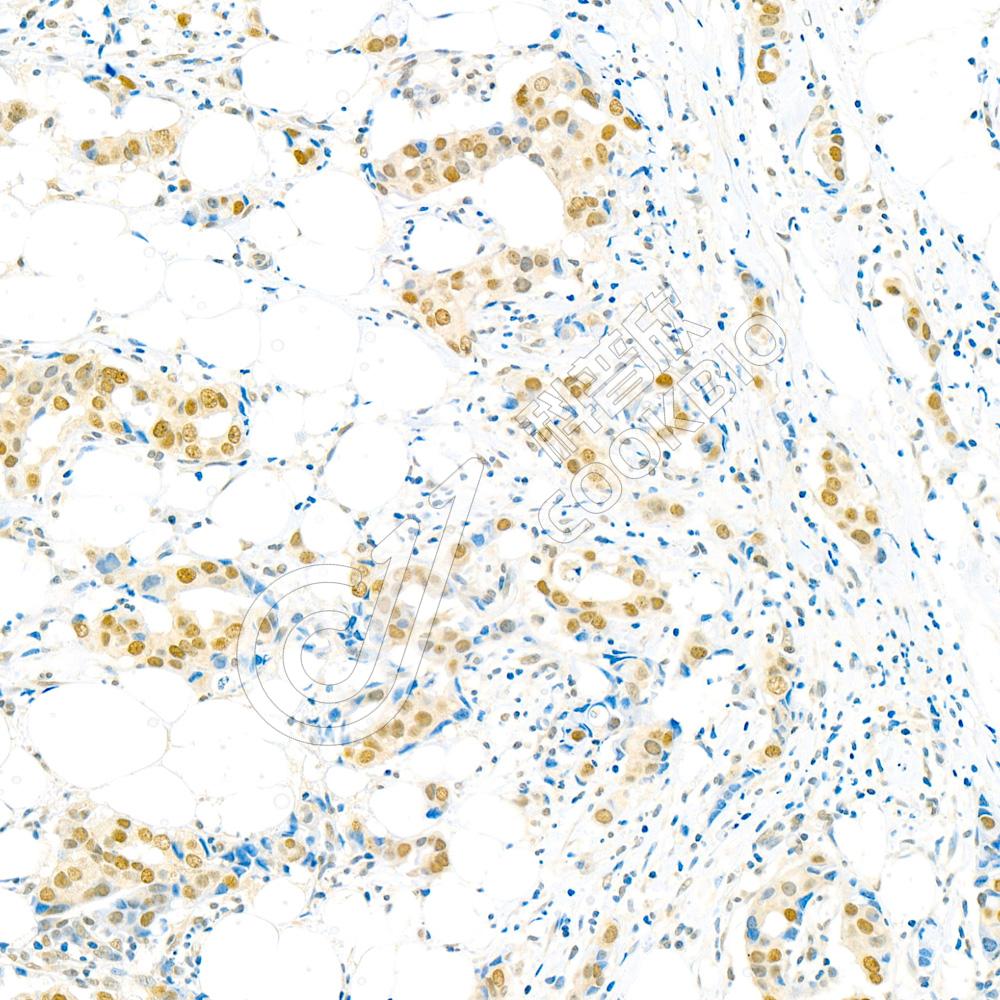

Anti-Src 兔多克隆抗体

兔多抗

其它

IHC/IF

H,M,R

货号:K1333105-100

规格:100 μL

¥ 1900

K1333105-100

100 μL